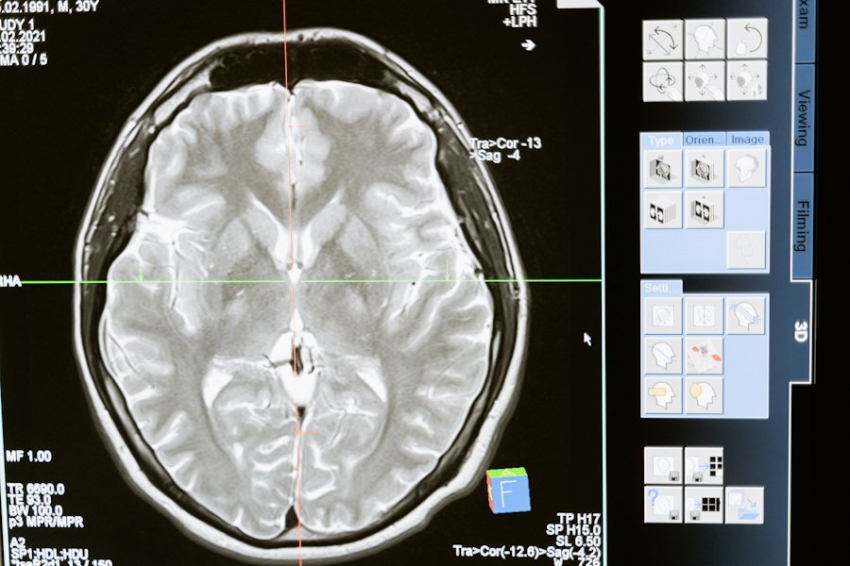

Фото из открытых источников

В исследовании, итоги которого опубликованы в журнале Nature, эксперты записали активность отдельных нейронов у людей. Оказалось, что в определённых клетках мозга идёт активация деятельности в зависимости от того, как человек переживает тот или иной опыт.

Мозг, уверяют авторы исследования, способен хранить уникальные паттерны активации нейронов даже после завершения события. Что позволяет мозгу быстро восстанавливать их в состоянии покоя. А значит, и применять в алгоритмах выстраивания ассоциаций, логических цепочек, которые и помогают предсказывать будущие события на основе прошлых переживаний. Здесь речь не идёт об откровениях, а, скорее, о логичном расчете, математически выверенном анализе.

В опыте приняли участие 17 человек с эпилепсией, которым имплантировали в мозг электроды. Эксперты регистрировали уровни активности нейронов в процессе выполнения заданий. Участники отсматривали множество изображений, дабы определить, человек или предмет изображены на них.

В результате нейроны в специальных областях мозга выстроили определенную последовательность, стали функционировать в соответствии с порядком отображаемых изображений. То есть, впервые опытным путем показано, что мозг применяет аналогичные механизмы для представления о совершенно разных типах информации: о пространстве и времени.